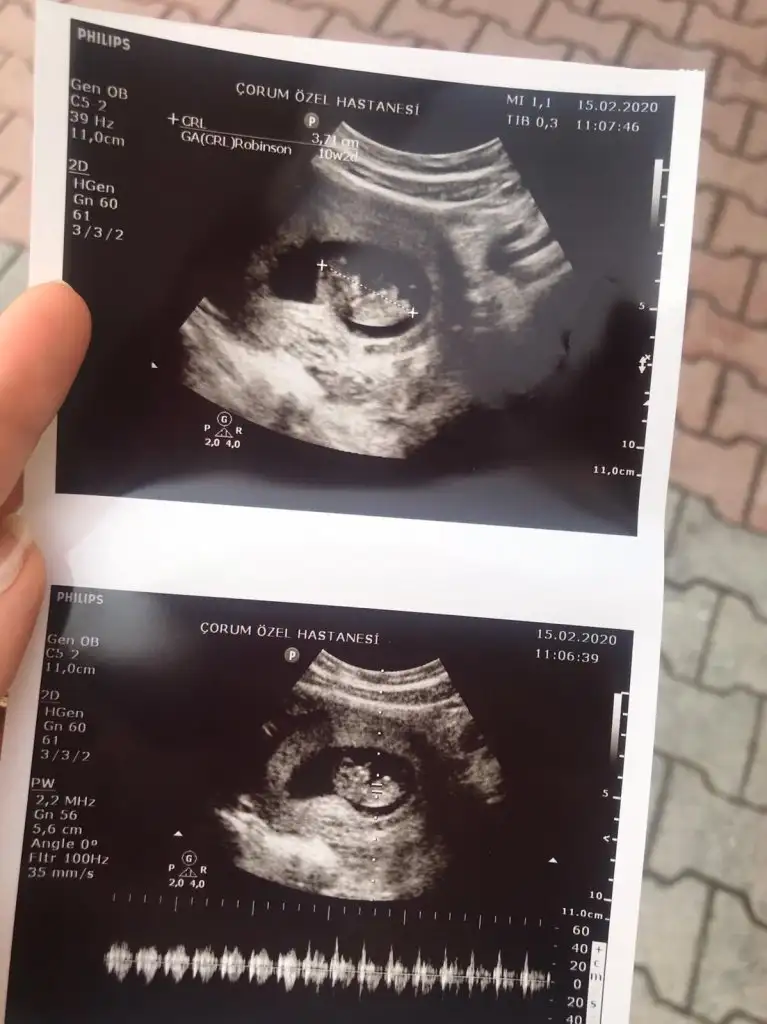

IMG-20200215-WA0001.webp

10+2yiz ama burda daha dr kontrolumüze var ben çıkıntı falan göremedim kızlar ya yardim edin 😅